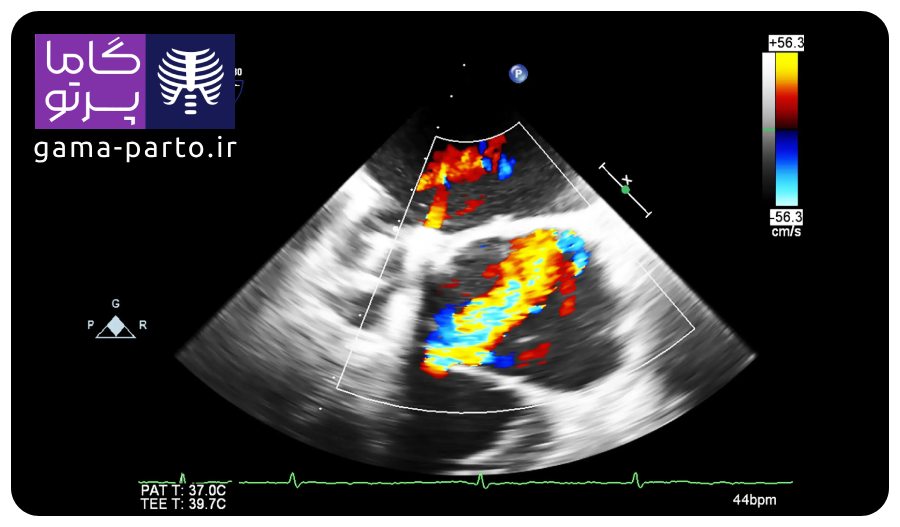

مجموعه گاما پرتو با استفاده از دستگاه پرتابل اکو قلب، انواع خدمات اکوکاردیوگرافی شامل: اکو دوبعدی، اکو داپلر رنگی، اکوی کامل کالر داپلر (بررسی فشار حفرات قلب) و اکوی قفسه‌ای (ترانس توراسیک) را به‌صورت حرفه‌ای در منزل ارائه می‌دهد.